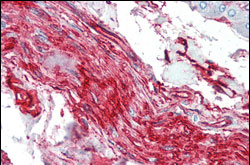

Figure 2: Immunohistochemical analysis of paraffin-embedded human nerve and ganglion cells using S100A10/P11 mouse mAb.